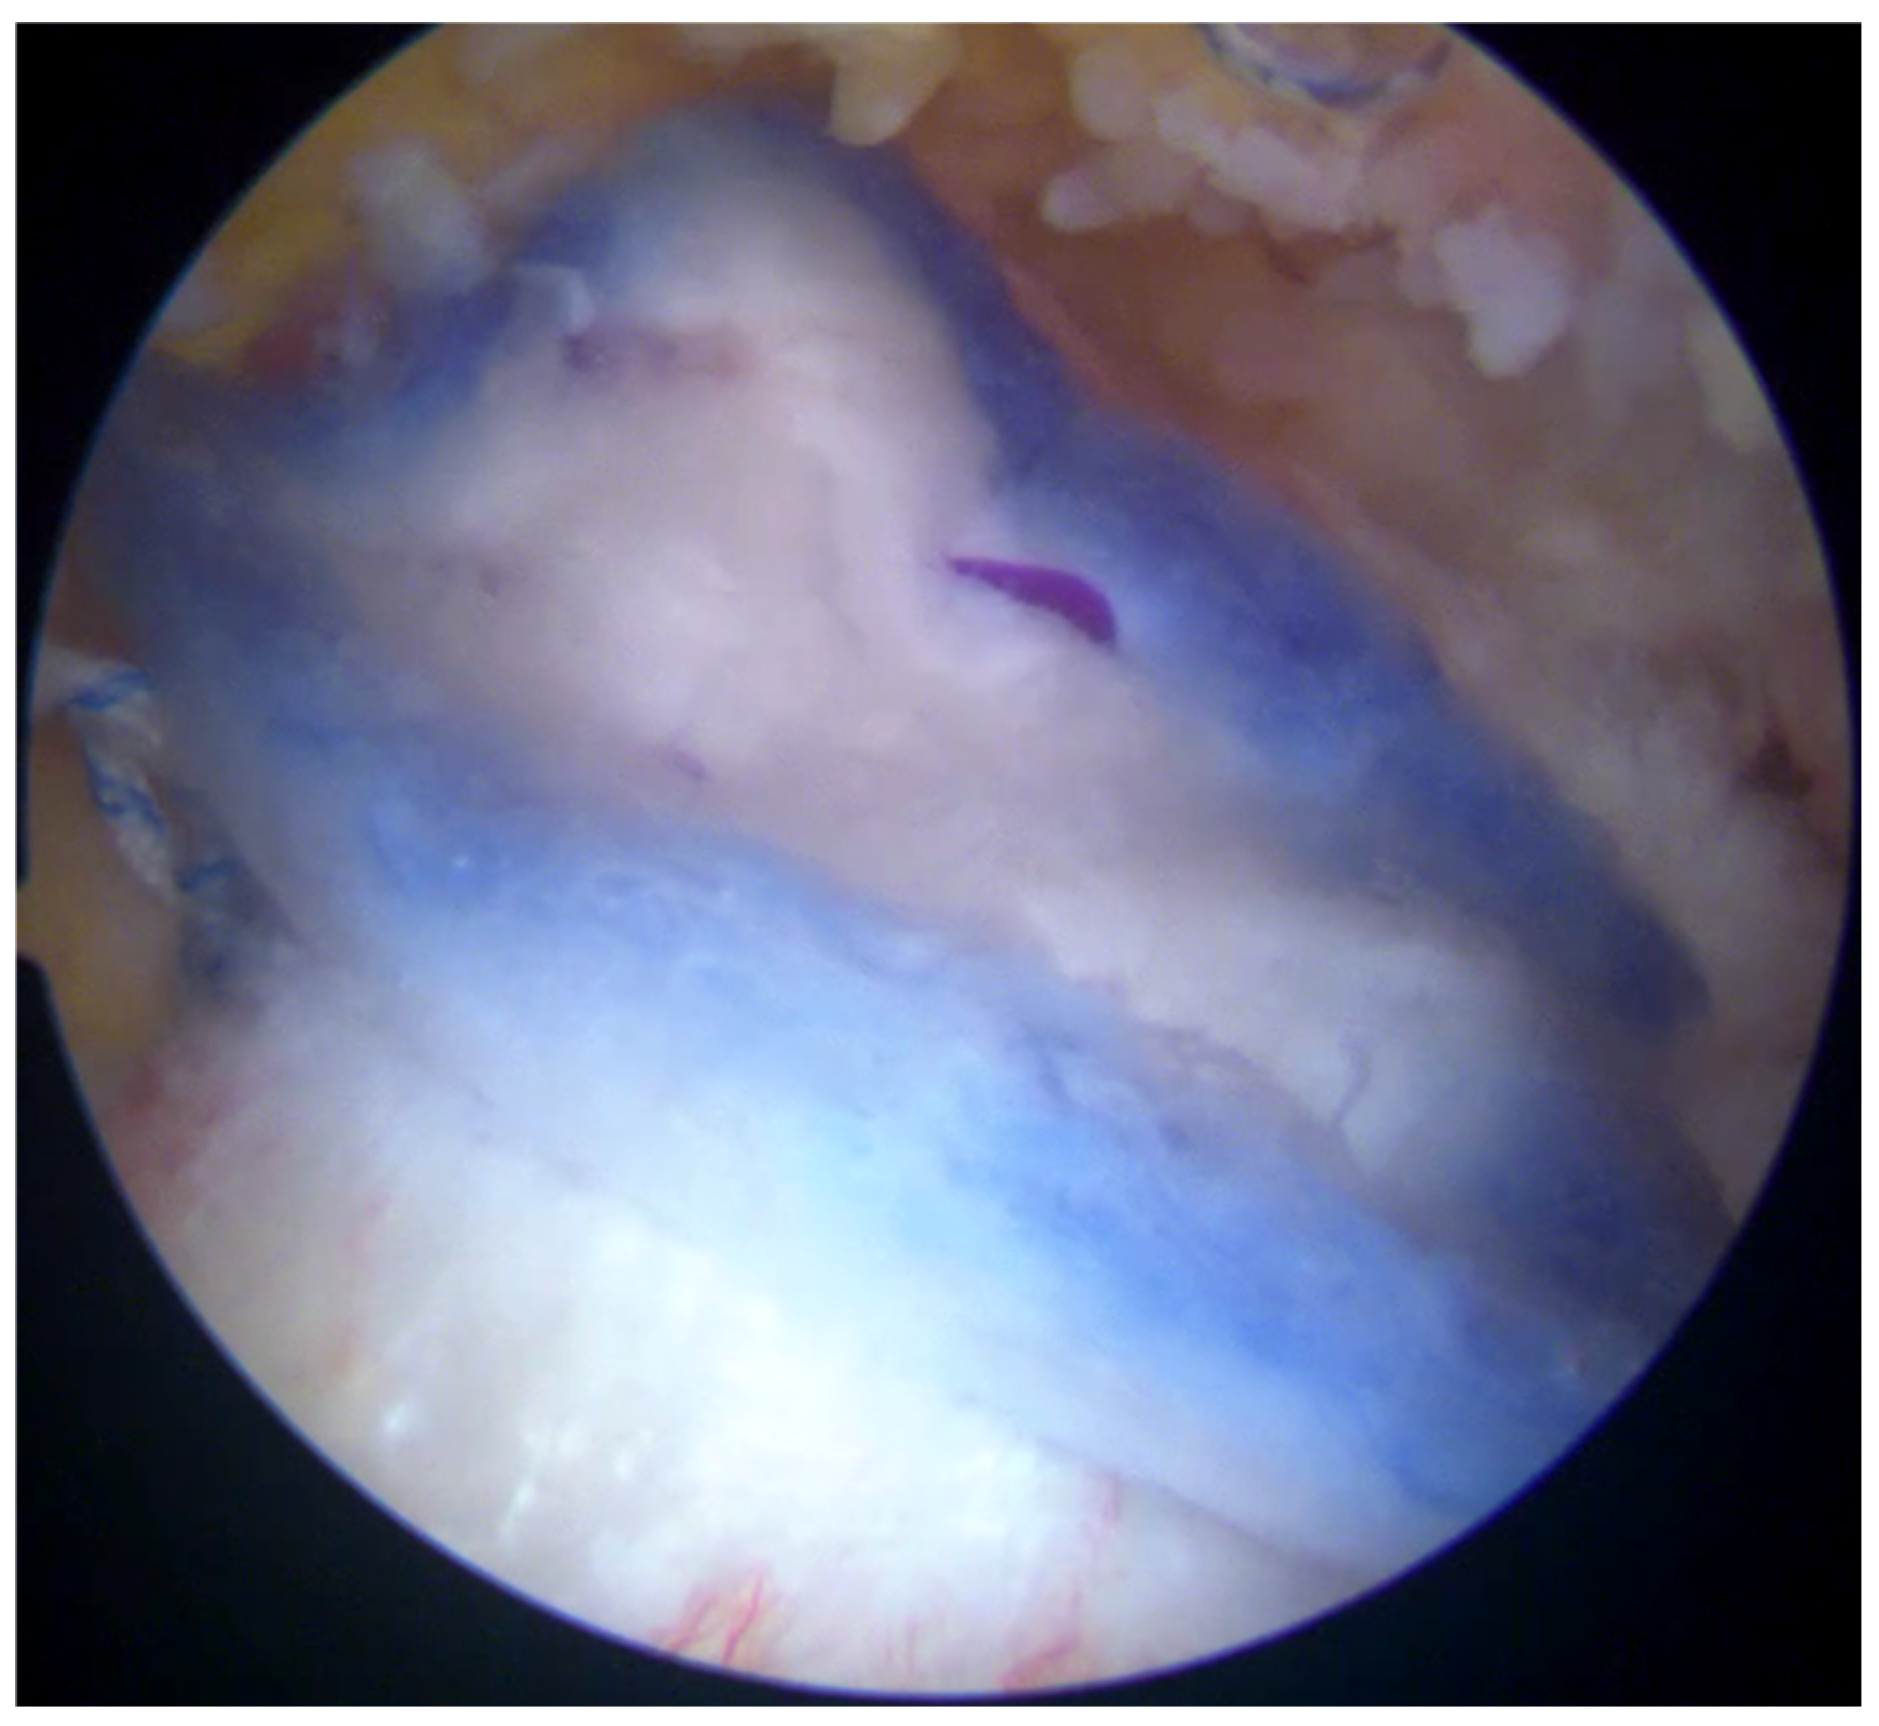

At six months after the surgery, a new MRI was performed, showing the reaction induced by the implant, with the progressive formation of tendon-like tissue (Figure 9).

Figure 9.

Postoperative MRI at 6 months after surgery, showing progressive formation of new tendon-like tissue with improvement of tendon thickness.

The effects of biological augmentation are evident in histologic studies and MRI. After 6 months, there is no histological evidence of the Regeneten implant remaining and the neotendon is indistinguishable from the native tendon on MRI, both in partial tears treated with isolated bioinductive repair and in full-thickness tears managed with complete augmented repair [5]. Schlegel et al. found that 87% of partial tears treated solely with bioinductive repair using Regeneten showed more than a 50% reduction in tear size in MRI after 24 months, along with a significant increase in tendon thickness. Additionally, no significant differences in clinical outcomes, tear healing, or tendon thickness were observed based on the location of the tear [7,19].

The subjective improvements and the improvements in the range of motion and tendon regeneration observed in this case are encouraging and suggest that the bioinductive implant may have contributed to enhanced healing. While a direct comparison with patients undergoing mechanical repair alone is not possible in this case report, the observed outcomes appear comparable to, or potentially better than, those reported in studies evaluating traditional repair techniques. Specifically, the patient achieved a near-full range of motion and a significant reduction in pain at 6 months post-surgery, which is a positive outcome. The observed outcomes in this case are consistent with the manufacturer’s reported data for the Regeneten implant, which indicate that the implant can promote tendon healing and improve clinical outcomes in patients with rotator cuff tears. Specifically, Smith and Nephew reports that Regeneten reduced the size of partial-thickness rotator cuff tears by over 50% in all tear locations [7]. The positive results observed in this case further support the use of Regeneten for the augmentation of rotator cuff repair. However, further research is needed to directly compare the outcomes of bioinductive implants with mechanical repair alone and other augmentation techniques.